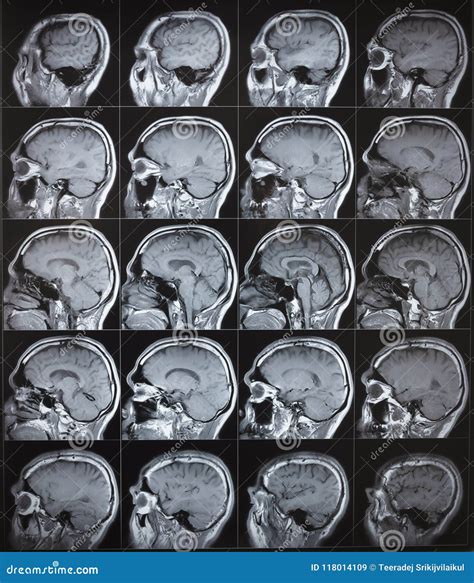

Receiving the results of a neurological examination can be an anxious experience, especially when waiting for clarity regarding your health. Understanding what constitutes a normal brain MRI is a critical step in demystifying the diagnostic process. A magnetic resonance imaging (MRI) scan of the brain is a non-invasive, painless procedure that uses magnetic fields and radio waves to create detailed, high-resolution images of the brain's structures. When a radiologist reviews these images and labels them as "normal," it signifies that the anatomy of the brain appears consistent with healthy, standard expectations for your age and demographic, with no evidence of major structural abnormalities, tumors, or lesions.

Physicians typically order a brain MRI to investigate a wide range of symptoms, including persistent headaches, seizures, dizziness, memory loss, or sudden behavioral changes. Because it provides exceptional soft-tissue contrast, it is superior to CT scans for visualizing complex brain anatomy. A normal brain MRI serves as a fundamental benchmark, helping clinicians rule out serious underlying conditions such as strokes, multiple sclerosis, brain tumors, or anatomical defects.

During the scan, you will lie on a motorized table that slides into a tube-shaped machine. The process usually takes between 30 to 60 minutes. You will hear loud clicking or thumping sounds, which are normal occurrences as the magnetic coils activate. Many facilities provide earplugs or headphones to help you stay comfortable during the duration of the scan.